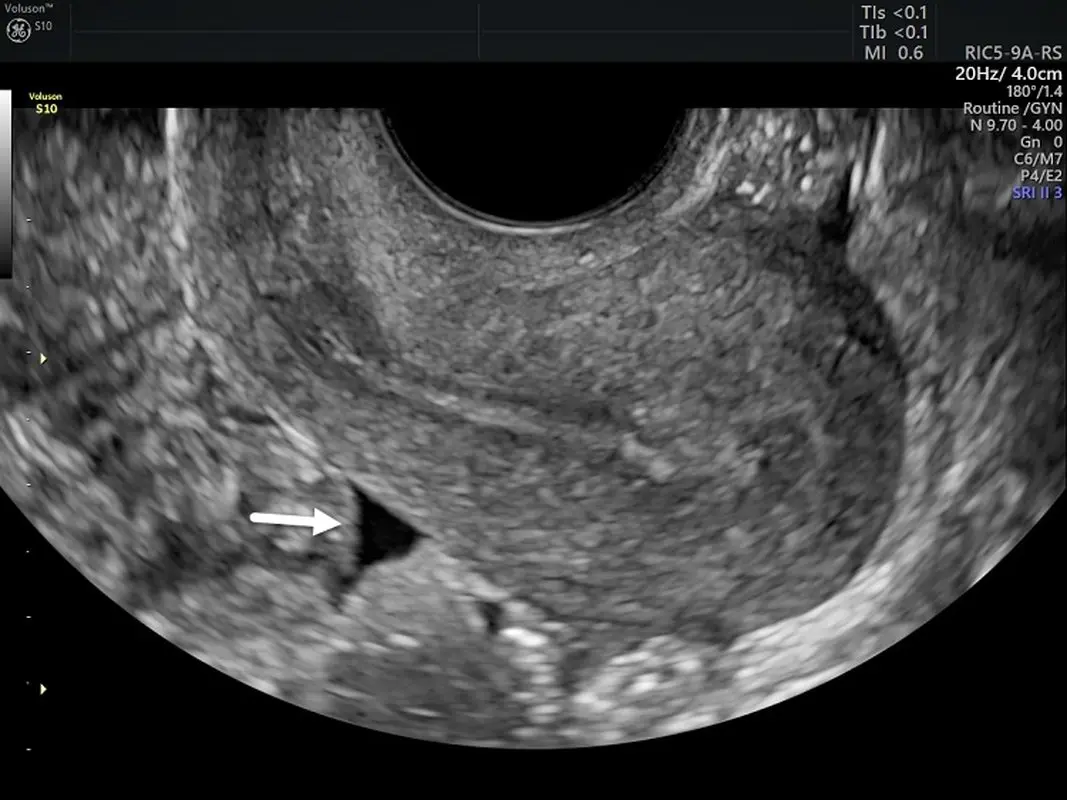

سونوگرافی ترانس واژینال

سونوگرافی ترانس واژینال نشان میدهد که آیا مایع پشت رحم وجود دارد یا نه. یک پروب در واژن قرار داده میشود تا تصاویر سونوگرافی با جزئیات بیشتری را بگیرد. اگر مایع پیدا شد، ممکن است به آزمایشهای بیشتری نیاز داشته باشید.